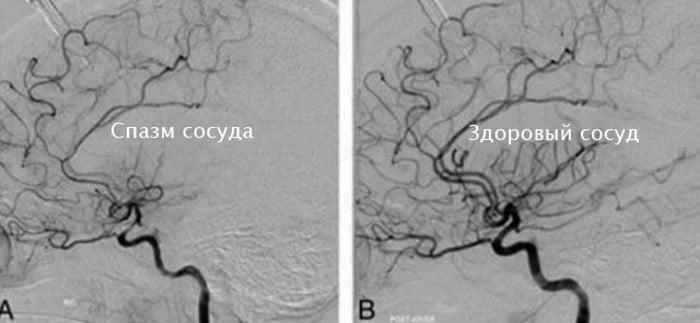

- ангиография с введением контрастного вещества;

В ходе диагностики спазм сосудов головного мозга дифференцируется от схожих по симптоматике цереброваскулярных патологий. К ним относятся транзиторная ишемическая атака, инсульты обоих типов, гидроцефалия (остро развивающаяся при опухоли), прочие ликвородинамические нарушения.